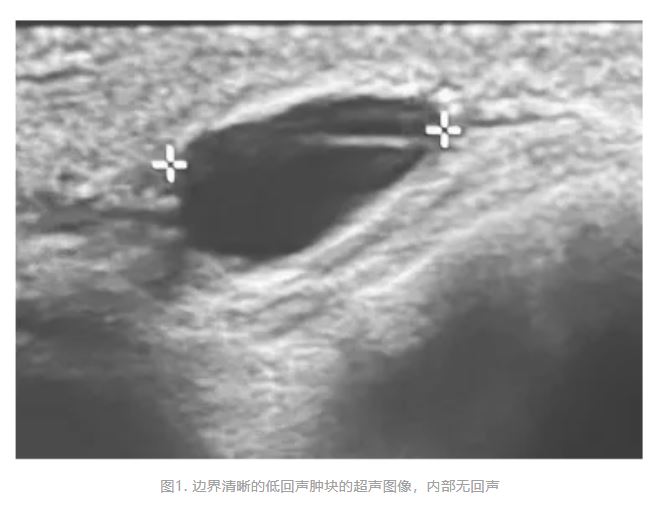

和超声检查;结果显示双侧性质未定的颌下结节,被描述为可能为囊性(图1)。考虑到恶性肿瘤的可能性,患者自行转诊至纽约州纽约市西奈山伊坎医学院的耳鼻喉科门诊。

在用于引导细针穿刺活检的超声检查中,在IB区双侧可见浅表无回声、边界清晰的病变,几乎没有内部回声或血管。未发现淋巴结门。使用27号针头从左侧病变获取样本。病变对针头感觉坚硬,且完全可移动。即时显微镜检查结果显示有角状透明嗜双色性非细胞物质,类似于软骨碎片,因此使用25号针头进行了第二次穿刺。第二次穿刺获得了更丰富但类似的非细胞物质,并伴有异物巨细胞反应(图2)。未见淋巴组织,亦未见可疑细胞。患者确认,大约18个月前,他的牙医为了下颌线塑形,在其双侧下颌旁区域注射了填充剂。患者不确定注射量和填充剂品牌,但他回忆说是由透明质酸制成的。没有其他注射史。